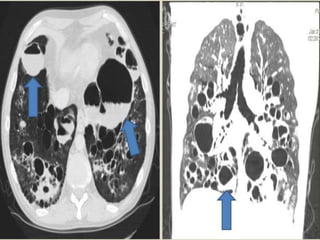

 CT is the study of choice with a sensitivity of

up to 97% and a specificity up to 99% Signet

ring appearance on CT : normally, the vessel is

larger than the corresponding bronchus

 In bronchiectasis, the bronchus is larger than

the corresponding vessel

 “Tramlines” or “honeycombing” represents

dilated, thickened bronchial walls

 Signet ring appearance on CT: normally, the

vessel is larger than the corresponding

bronchus; in bronchiectasis, the bronchus is

larger than the corresponding vessel.

 Bronchial dilation, the cardinal sign of

bronchiectasis, is characterised on HRCT by a

bronchoarterial ratio (BAR) of .1, lack of

bronchial tapering, and visibility of airways

within 1 cm of the pleural surface or abutting

the mediastinal pleural surface.

dilated, thickened bronchial walls.